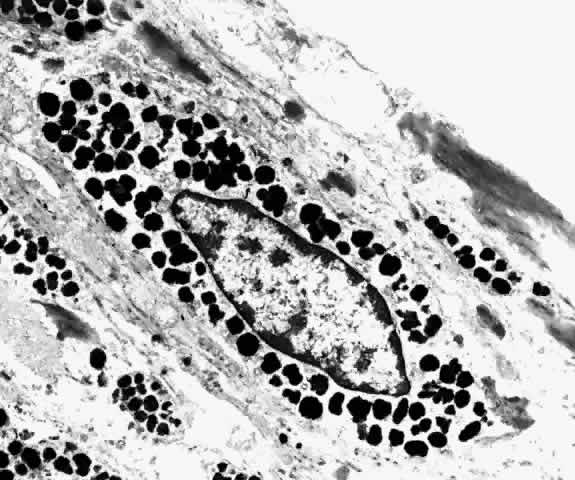

Forming an almost continuous layer in the outer choroid, melanocytes are most abundant near the optic nerve and less dense peripherally.52 The nuclei are oval and surrounded by a double membrane. The chromatin is evenly dispersed, and nucleoli are present.17 The cytoplasm is heavily filled with oval, membrane-bound melanin granules, and as much as 70% of the cytoplasm may be occupied by melanosomes (Figs. 29 and 30).22

Fig. 29. Choroidal melanocytes (mel) intermixed with fibrocytes (f). Spindle-shaped melanocytes have elongated nuclei (s), polyhedral melanocytes have oval nuclei (p), and both types of melanocytes have prominent intracytoplasmic melanin pigment granules. (× 4750)

Fig. 30. Fusiform choroidal melanocyte with tapered nucleus (f) and abundant intracytoplasmic pigment granules. (× 9000)

The melanocytes in the middle choroidal layers are star shaped, the cell bodies smaller, and the processes long and thin, stretching out as tentacles from the cell body. The processes connect with cells in adjoining layers but do not seem to plunge deeply across several lamellae into the more inner layers. The melanosomes, 0.3 to 0.4 μm in diameter, are all about the same size in a given person, and are fine and evenly distributed in the cytoplasm.52 The melanin granules are lighter brown and smaller than in the RPE. The cytoplasm also contains free ribonucleic acid granules, a few mitochondria, Golgi apparatus, rough endoplasmic reticulum, vesicular and lamellar elements, and centrioles. Some melanocytes contain many mitochondria and smaller melanin granules, less than 0.2 μm in diameter.5 Freeze-fractured melanocytes reveal melanosomes as membrane-limited organelles with a uniform, finely divided, particulate inner structure and no discernible internal arrangement.63